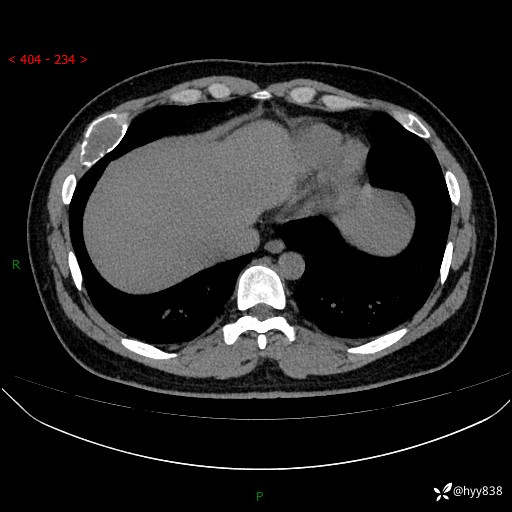

胸部CT平扫